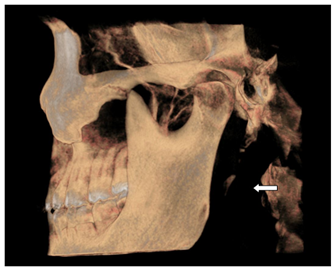

Figure 7 Shows Elongated SP.

Of the 87 images examined 30% showed elongated styloid (>35mm) and there was no significant statistical difference between the length of the elongated SP and MLA and APA (p=0.29, 0.24). Of the 3 types of morphological variation in the type of ossification of SP, on the right side 24SHCs (57.1%) showed single segment ossification, 15 SHCs (35.7%) showed two segment ossification and 3SHCs (7.1%) showed three segment ossification (Table 8). On the left side 23 SHCs (51.1%) showed single segment ossification, 18SHCs (40%) showed two segment ossification and 4SHCs (8.8%) showed three segment ossifications (Table 9).